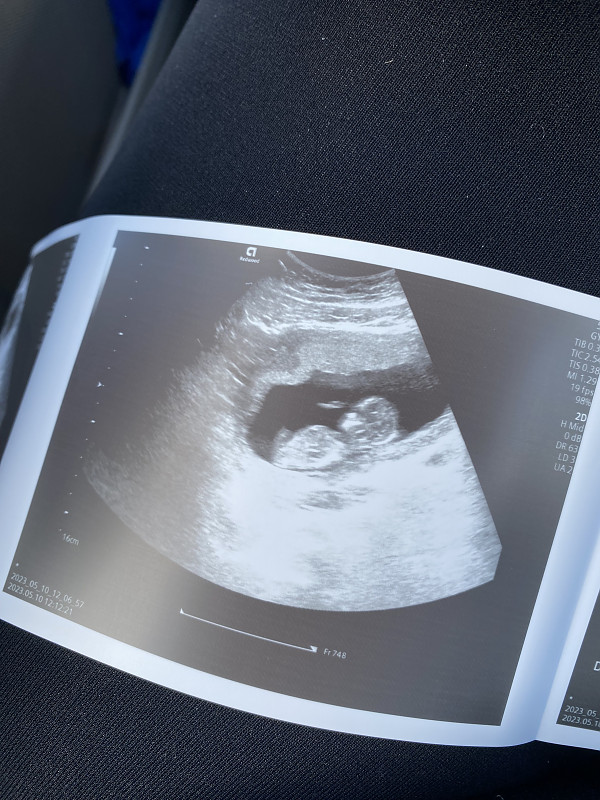

Ramzio vaisiaus lyties nustatymo teorija

Pagal Ramzio teoriją kūdikio lytį galima nustatyti labai anksti, 6-8 nėštumo savaitę iš pradėjusios formuotis placentos vietos. Skaityti visą straipsnį